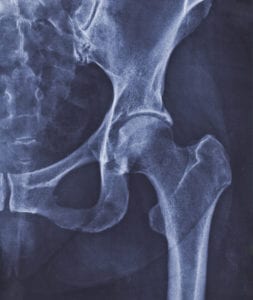

Common Types of Hip Surgeries

For hip pain that fails to respond to conservative treatments, your doctor may recommend hip surgery. Often the last resort for patients dogged with hip problems, surgery can be a life-saver for many. The two most common types of hip surgeries used to treat orthopedic hip conditions are either Read More